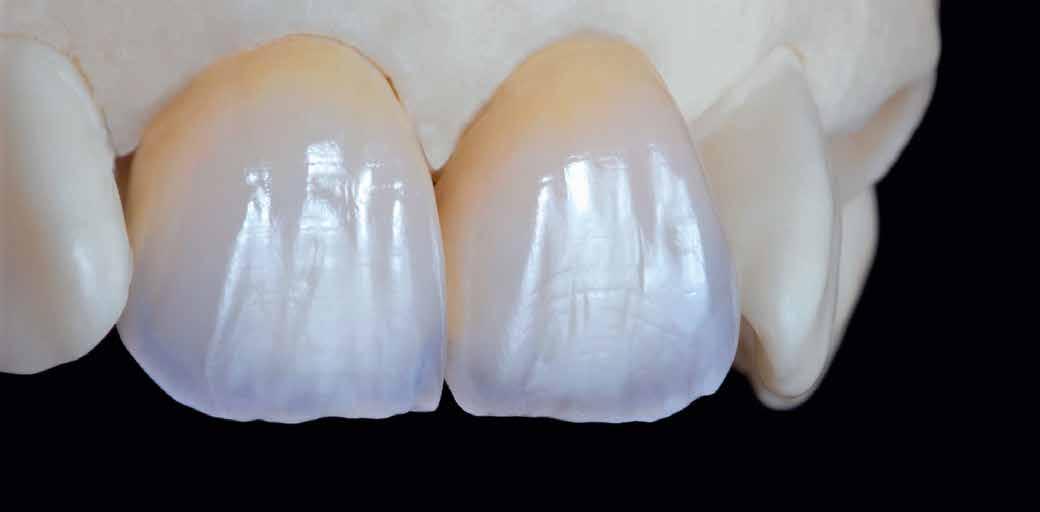

A digitális mosolytervezés eredményét át lehet alakítani hagyományos vagy virtuális modellé, ami egyszerűbbé teszi az eltervezett kezelések végrehajtását, például egy CAD/CAM technológiával készült pótlás elkészítését. Az adhezív rendszerek és a fényáteresztő anyagok együttes használata lehetővé teszi a minimál invazív preparációs technika alkalmazását. A lithium-diszilikáthoz hasonló anyagok esztétikai tulajdonságai a saját fogakhoz hasonló megjelenést kölcsönöznek a restaurátumoknak, ami jelentős mértékben hozzájárul az esztétikus végeredményhez.

A végső restaurátumokat (héjakat és koronákat) Ce-

ramill Mind tervező program segítségével (AmannGirrbach) digitálisan megtervezték, majd frézgép segítségével (CeramillMotion 2, AmannGirrbach) li thium-diszilikát tömbökből (VITABLOCS TriLuxe forte for CeramillMotion 2, AmannGirrbach) kifaragták (10. ábra). Miután a fogpróba során ellenőrizték és megfelelőnek találták a pótlások széli záródásának a pontosságát, valamint az elkészült restaurátumok esztétikai megjelenését, ezután egy ajak- és szájterpesz került felhelyezésre (OptraGate, IvoclarVivadent).